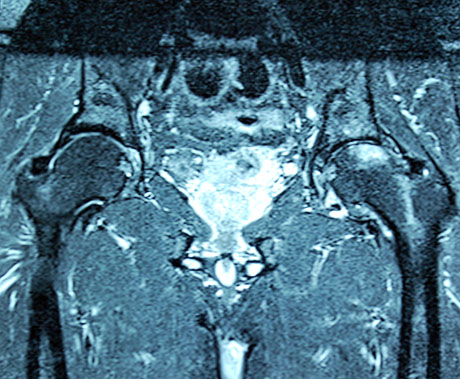

Magnetic resonance imaging of the hip after 5 months post-op and the injection of stem cells. Osteonecrosis of the femoral head has subsided completely. The patient is fully cured.